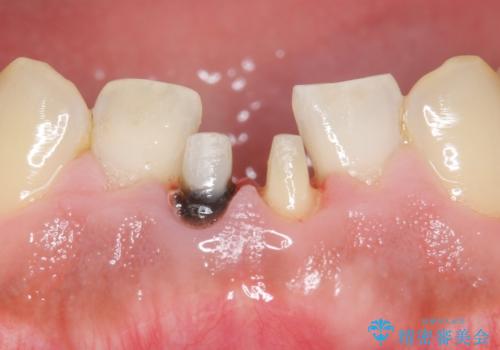

- 下の前歯の色が気になることを主訴に来院された患者様です。

下の前歯は金属の土台により黒くなり、隣の歯も神経が死んで暗く変色していました。

神経が死んでいる歯の根管治療を行った後、セラミッククラウンによる補綴治療を行いました。

比較的短期間(2ヶ月、来院回数:5回)で治療が終わったこと、また自然な仕上がりと使用感にご満足頂けました。

ジルコニアクラウン スタンダード